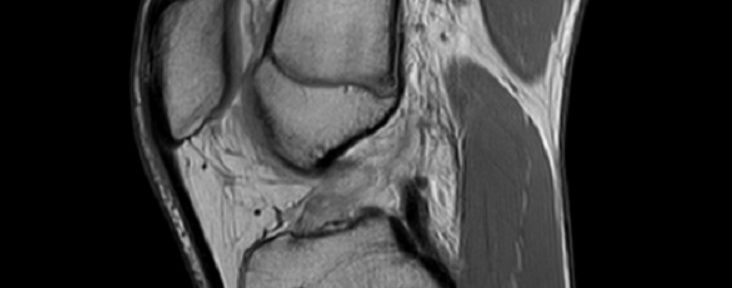

- 2023年3月30日:MRI①=前十字靭帯(ACL)完全断裂

- 独立読影(3名):3/3名一致で Ihara分類 Ⅲ(断端の変位を伴う断裂)

【Ihara分類 注釈】Ⅰ=直線的な断裂/Ⅱ=湾曲した断裂(単純完全断裂に相当)/Ⅲ=断端の変位を伴う断裂/Ⅳ=断端が不明瞭な断裂

2回目のMRI(約4か月後)

- 撮影日:2023年8月2日(MRI②)

- 独立読影(3名):3/3名一致で ACLOAS 2型

- 所見:連続性は回復。太さは完全ではないが、一定の太さと緊張を獲得

【ACLOAS(native 前十字靭帯)注釈】0=正常(低信号・規則的)/1=肥厚や高信号を伴うが形状・連続性は正常/2=菲薄化・伸長はあるが連続性保持/3=欠損し連続性消失